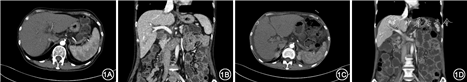

患者女性,56岁,因“腹泻7个月,发现肝功能异常6个月”,于2019年6月14日收入北京协和医院消化科。患者2018年11月于古巴出差后出现腹泻,黄色水样便6~8次/d,偶见未消化食物、油滴,脐周钝痛,排便后缓解,伴乏力、纳差,无发热,同行者无类似症状。2019年1月出现双下肢对称可凹性水肿,外院查血常规、尿常规及粪便常规+潜血均正常;血生化:白蛋白23 g/L,丙氨酸转氨酶(ALT)173 U/L,天冬氨酸转氨酶(AST)168 U/L,γ-谷氨酰转肽酶(GGT)186 U/L,碱性磷酸酶(ALP)231 U/L,乳酸脱氢酶(LDH)575 U/L,胆红素正常;癌抗原19-9(CA19-9)646 U/ml,癌胚抗原(CEA)11 μg/L;血铜蓝蛋白(-)。腹盆增强CT(图1A):胰腺萎缩;肝脾饱满;肝门区、肠系膜根部见多发淋巴结肿大。多次输注白蛋白,监测白蛋白20~30 g/L。2019年3月就诊我院,查24 h尿蛋白定量 0.16 g;红细胞沉降率10 mm/1h,超敏C反应蛋白(hsCRP)4.08 μg/L;甲肝抗体、乙肝五项、丙肝抗体、戊肝抗体、巨细胞病毒DNA、EB病毒DNA、细小病毒B19、肥达外斐反应试验均(-)。血免疫球蛋白G(IgG)22 g/L(IgG4正常),C3 0.573 g/L,C4正常,Coombs试验弱阳性;抗核抗体(ANA)均质型1∶320;余抗核抗体谱、抗可提取核抗原(ENA)抗体谱、自身免疫性肝炎相关抗体谱、原发性胆汁性胆管炎相关自身抗体谱、抗磷脂抗体谱、狼疮抗凝物均(-);血清肿瘤标志物:CA19-9 323 U/ml,CEA 11.5 μg/L,癌抗原125(CA125) 323 U/ml,细胞角蛋白19的可溶性片段(Cyfra211) 11.6 μg/L;血、尿免疫固定电泳、血、24h尿轻链(-);甲状腺功能、胃泌素(-);PET-CT:肠系膜根部脂肪密度增高,肠系膜上及腹膜后多发代谢增高淋巴结,部分饱满(0.6~1.7 cm,SUVmax2.5);肝脾饱满,骨髓弥漫代谢轻度增高(SUVmax 2.0);胸腹盆积液。胃镜、结肠镜检查未见明显异常。超声内镜引导下穿刺腹膜后淋巴结,病理未见瘤细胞。予止泻、保肝、调节肠道菌群治疗后腹泻缓解,每日排2次黄色成形软便,肝功能较前改善。2019年5月再次腹泻,排水样便3~5次/d,每次量100~200 ml。与麸质饮食无关,伴脐周疼痛、纳差。为进一步诊治收入病房。起病以来,患者精神、睡眠、食欲差,小便如常。病来体重下降15 kg。否认皮疹、光过敏、口眼干、关节痛、口腔溃疡、雷诺现象。既往史:1型糖尿病27年,长期胰岛素控制,偶有低血糖发作。高血压7年,药物治疗血压控制可。患者起病前1个月曾行体检,肝功能正常。婚育史、个人史、家族史无殊。

体格检查:体温36.3 ℃,脉搏94次/min,血压105/75 mmHg(1 mmHg=0.133 kPa),呼吸20次/min,体重指数(BMI)15 kg/m2,全身皮肤、巩膜未见黄染,浅表淋巴结未及,颈静脉无怒张,心肺查体无特殊。腹软,腹膨隆,无压痛、反跳痛及肌紧张,Murphy征(-),移动性浊音(+),肠鸣音3次/min,双膝以下对称可凹性水肿。实验室检查:血常规:白细胞8.19×109/L,中性粒细胞58.6%,血红蛋白111 g/L,血小板212×109/L;血涂片未见异常;尿常规、粪便常规+潜血均(-),粪便镜检可见脂肪滴,苏丹Ⅲ染色(+);D-木糖吸收试验:0.4 g/5h(>1.2);生化:白蛋白 27 g/L,ALT 44 U/L,AST 37 U/L,ALP 138 U/L,LDH 285 U/L,胆红素正常,胰胰腺功能正常;血清铁蛋白、叶酸、VitB12正常;凝血:凝血酶原时间(PT)17.5 s,PT% 56%,活化部分凝血活酶时间(APTT)39.9 s,纤维蛋白原(Fbg) 0.76 g/L,纤维蛋白原降解产物(FDP)4.5 μg/ml,正浆纠正试验:即刻及2 h均可纠正;凝血因子Ⅷ活性122.5%;炎症因子:白细胞介素(IL)-6 18.2 ng/L,IL-8 70 ng/L,IL-10 9.1 ng/L,肿瘤坏死因子(TNF)α 39.8 ng/L;糖化血红蛋白 5.5%,C肽餐后2h<0.05 μg/L,胰岛素样生长因子1(IGF1)32 μg/L,1型糖尿病相关自身抗体谱(-);甲状腺功能、24h尿皮质醇、血皮质醇、促肾上腺皮质激素、醛固酮(-)。炎症性肠病抗体谱:抗胰腺腺泡细胞抗体-IgA (+)1︰20;麦胶病相关抗体谱(-); TB细胞亚群:T细胞绝对值 673个/μl,CD4阳性T细胞绝对值217个/μl,CD8阳性T细胞绝对值66个/μl,可见高比例CD4-CD8-T细胞。粪便病原学:粪便细菌、真菌、抗酸染色、痢疾、难辨梭菌毒素(-);粪便寄生虫卵、阿米巴滋养体及包囊、蓝氏贾第鞭毛虫抗原、滋养体及包囊、隐孢子虫抗原(-);粪便病原学核酸检测:弯曲菌、难辨梭菌毒素A/B、类志贺毗邻单胞菌、沙门菌、弧菌、霍乱弧菌、小肠结肠炎耶尔森菌、肠聚集大肠杆菌、肠产毒大肠杆菌,肠致病大肠杆菌,产志贺毒素大肠杆菌、志贺菌/肠侵袭大肠杆菌、隐孢子虫、圆孢球虫、溶组织阿米巴、贾第鞭毛虫、腺病毒F40/41、星状病毒、诺如病毒GⅠ/GⅡ,轮状病毒,札如病毒核酸(-)。行腹水穿刺送检腹水常规:比重1.018,白细胞306×106/L(多核51.3%),黎氏试验(+),腹水生化:总蛋白 18 g/L(血总蛋白61 g/L),白蛋白11 g/L(血白蛋白31 g/L),LDH 71 U/L(血LDH 253 U/L),腺苷脱氨酶(ADA)2.3 U/L,Glu、Cl、TG(-),抗酸染色、细菌、真菌、放线菌、奴卡氏菌(-)、瘤细胞(-)。腹盆增强CT+小肠重建(图1B):末段回肠、升结肠近段肠壁水肿;较2019年1月CT肝脾体积减小,新出现肝硬化改变,门脉期强化欠均匀;肝门区、肠系膜根部、腹膜后多发肿大淋巴结同前,腹盆腔积液;胰腺萎缩。肝区动态MRI:肝硬化,多发再生结节。生长抑素受体显像未见异常。胃镜:慢性浅表性胃炎,十二指肠球炎,病理:十二指肠黏膜显急性及慢性炎。胶囊内镜:小肠可见多发黏膜充血斑,散在小结节样改变。全麻下行腹腔镜腹腔淋巴结活检+肝活检,见腹腔大量腹水,肝脏表面萎缩成细颗粒结节状,肠管、腹膜肿胀,在空肠起始的系膜根部见多发肿大淋巴结,质地韧。取3枚直径1.5 cm淋巴结、部分肝脏左叶送检。病理:肠系膜根部淋巴结反应性增生;肝组织亚大块坏死后肝细胞结节状再生,伴细胆管增生。入院后口服胰酶肠溶胶囊联合肠道益生菌治疗,同时严格去麦胶饮食,患者腹泻无改善;同时予人纤维蛋白原输注、Vit K肌肉注射纠正凝血功能异常,间断静脉补液、人血白蛋白支持治疗。术后患者腹胀明显,考虑小肠细菌过度生长可能,予口服利福昔明治疗2周后腹泻改善,每日排2次不成形糊状便,内可见少量未消化食物残渣,下肢水肿缓解。